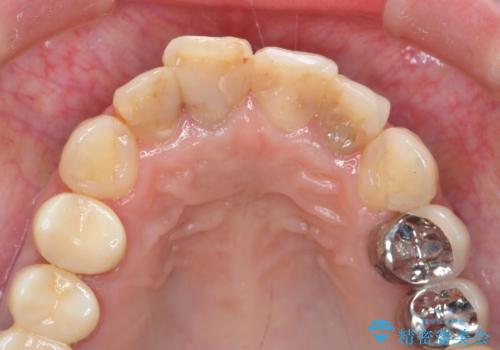

自然な歯の仕上がりに大変満足いただくことができました。